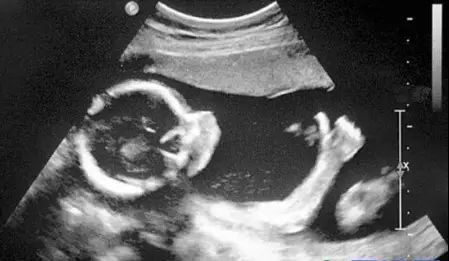

B超对于人体管腔的液体流动和腹腔脏器检查的敏感性较高,我们常常遇到的胆囊结石,肾结石,血管狭窄,心室功能等等检查,都是B超的用武之地。B超有着独特的优势,便携,可以在床边,甚至在手术中使用。此外,B超市利用超声波成像,也没有所谓的辐射。所以孕妇多采用B超检查。